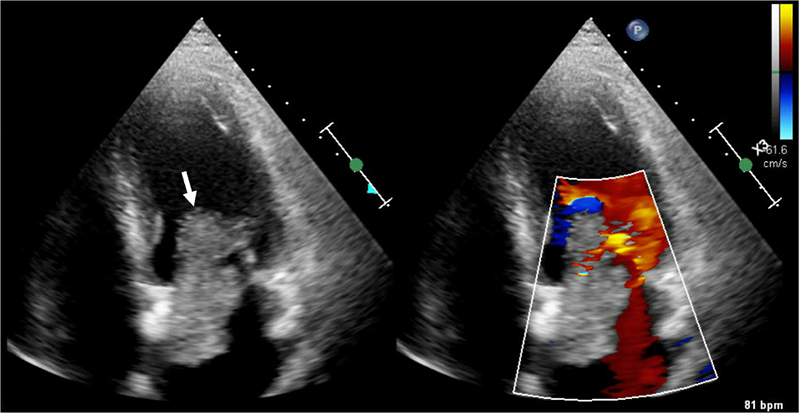

Figure 4. Transthoracic Echocardiogram. White arrow – 7.8 cm × 3.1 cm large echogenic structure in the left atrium attached to the interatrial septum protruding through mitral valve during diastole with mobile thrombus attached to the mass.

The next morning, patient experienced recurrent chest pain after returning from shower. She also reported bilateral leg heaviness and nausea, which partially improved with rest. However, her chest pain persisted, described as a pressure-like sensation worsened by deep inspiration. She remained hemodynamically stable (BP 130/87 mmHg, HR 83 bpm) but had increased oxygen requirement to 3 L/min via nasal cannula. Labs were remarkable for troponin T > 10000 ng/L. Repeat ECG showed increased ST-segment elevation in leads V2, I, and aVL with decreased voltage in leads II III, and aVF (Figure 1C). Transthoracic echocardiogram (TTE) demonstrated moderately reduced left ventricular systolic function (EF 35-39%), apical dyskinesis, anterior septal and mid anterior wall akinesis, mid lateral wall hypokinesis, reduced right ventricular systolic function, mild to moderate diastolic dysfunction, mild mitral regurgitation, and a 7.8 cm × 3.1 cm large echogenic structure in the left atrium attached to the interatrial septum protruding through mitral valve during diastole with mobile thrombus attached to the mass (Figure 4), suggestive of myxoma with superimposed thrombus.